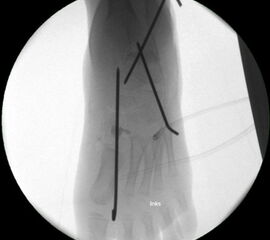

• Röntgenkontrolle (Bild 21,22).

• Im dargestellten Fall war zusätzlich eine plantarflektierende Cuneiforme mediale Osteotomie mit resorbierbarem Knochenersatz und eine Wadenmuskeldissektion nach Vulpius durchgeführt worden.

• Röntgen des dargestellten Falles 3 Monate post OP (Bild 25,26)